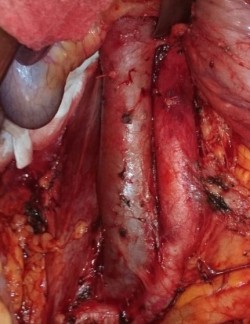

Расширенная нефрэктомия